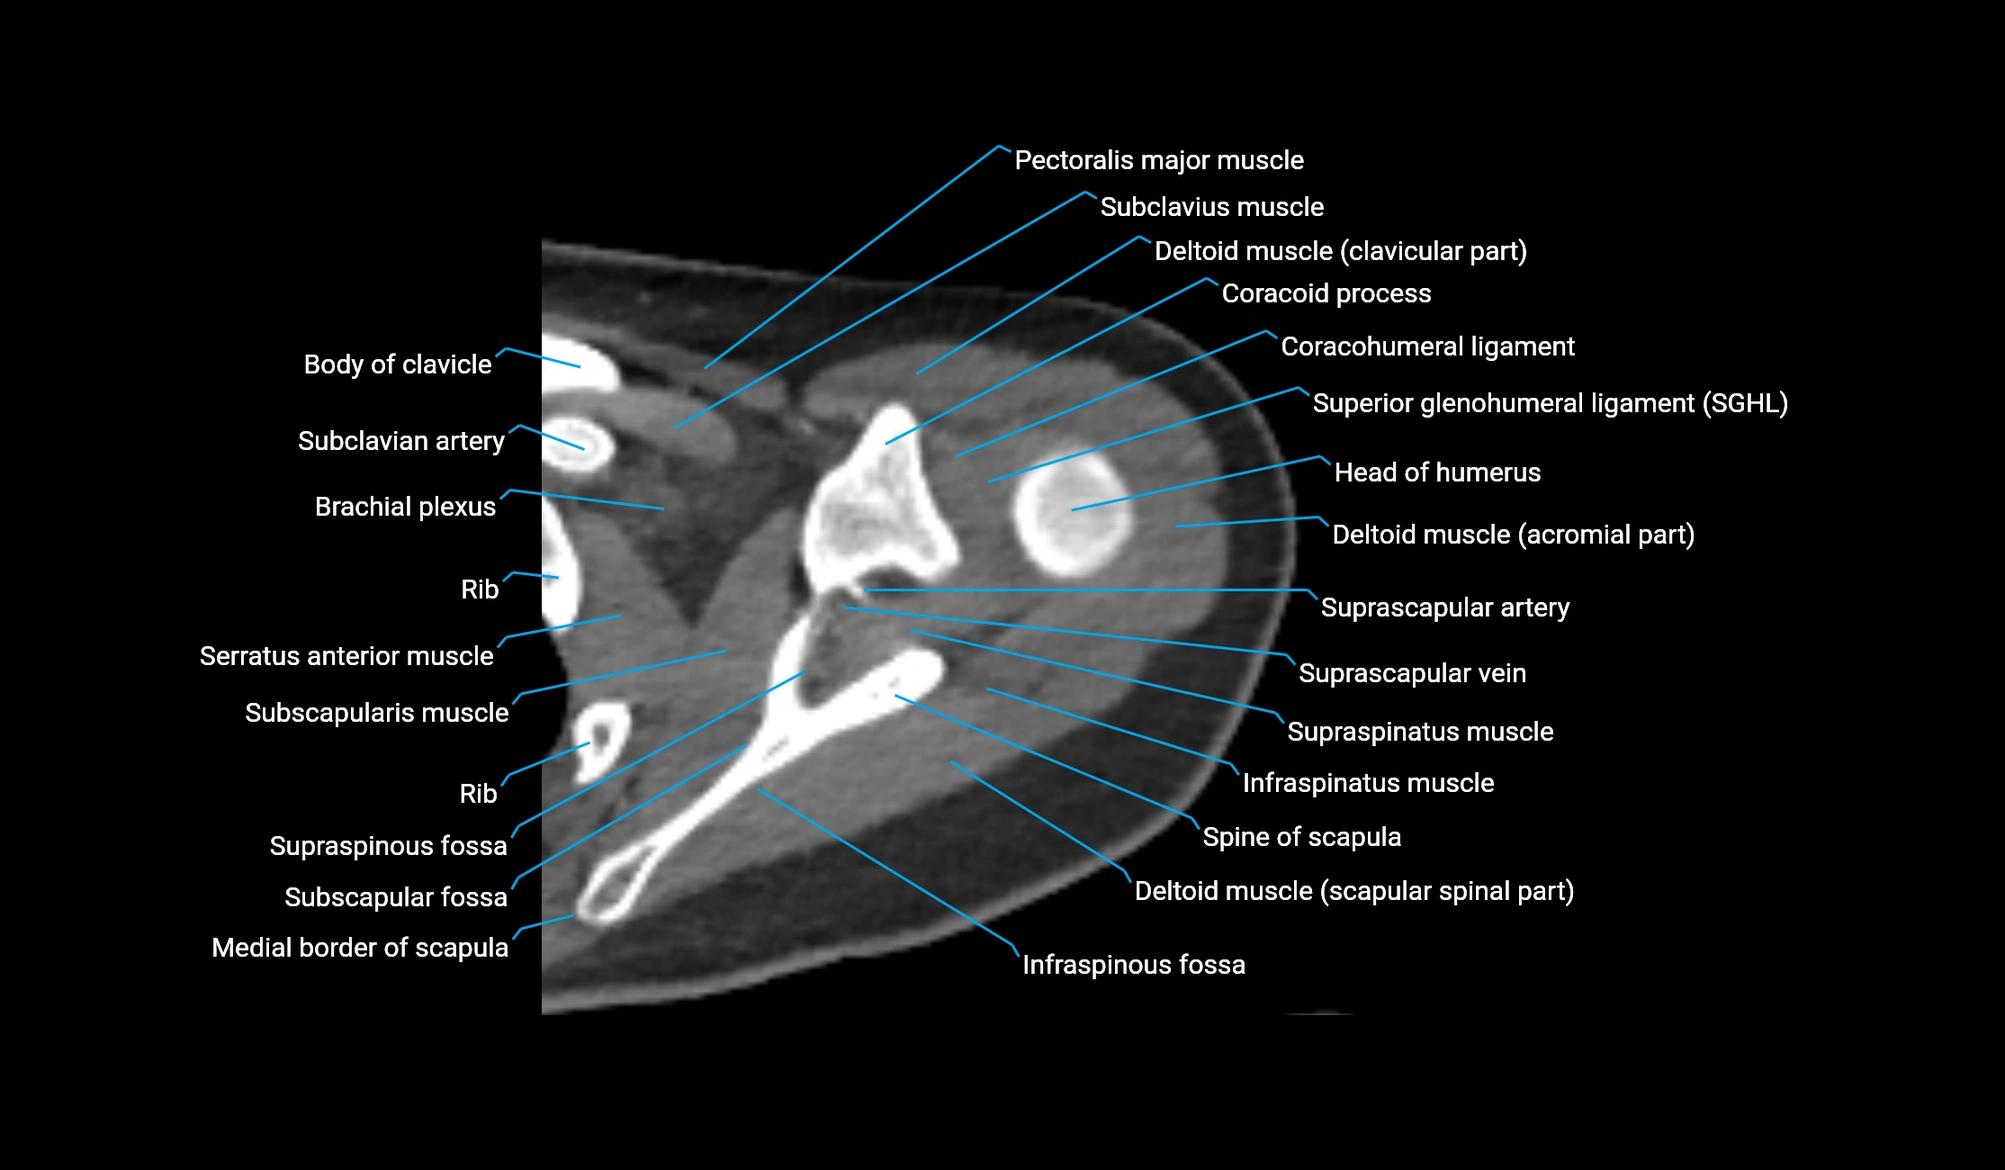

MRI image

CT image